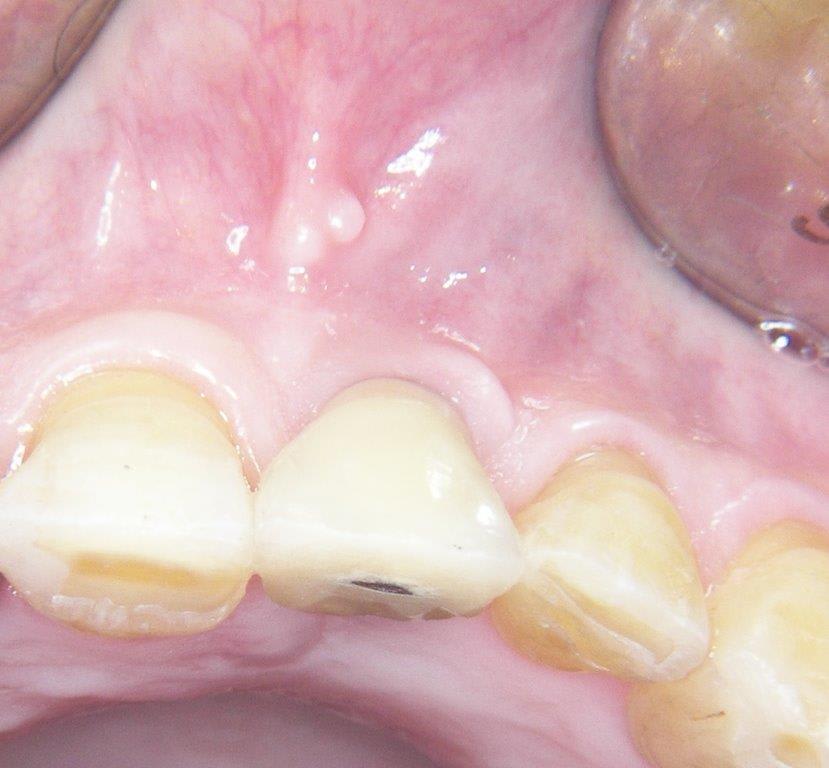

voilà prothèse moyenne mais aucun souci

un autre petit cas courant, agénésie 12/22